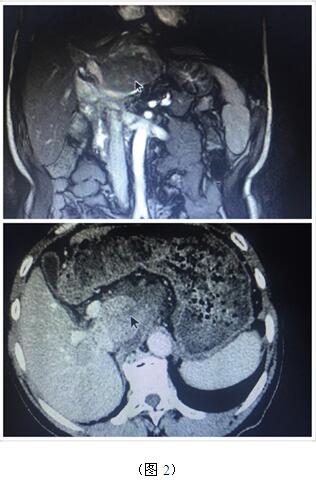

70歲高齡的曹奶奶是一個(gè)膽內(nèi)膽管結(jié)石、膽總管結(jié)石、膽囊結(jié)石的高齡患者,由于結(jié)石部位多發(fā)(圖1),當(dāng)?shù)蒯t(yī)院多次住院治療,均建議開(kāi)大刀切除部分肝臟;同樣患肝臟腫瘤的張爺爺,由于腫瘤位于肝臟尾葉,而且壓迫腹腔大血管(圖2),尋遍多家醫(yī)院都只能開(kāi)腹手術(shù)切除,聽(tīng)說(shuō)衡陽(yáng)市中心醫(yī)院腹腔鏡手術(shù)技術(shù)成熟遂慕名而來(lái)。肝膽外科周玖橋主任和李鑫副主任醫(yī)師仔細(xì)分析病情后決定為倆位患者行3D腹腔鏡手術(shù)。